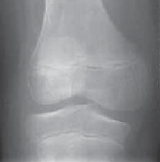

Chapter 25 Meniscoplasty for Discoid Lateral Meniscus Jay C. Albright DEFINITION A discoid meniscus is abnorm…